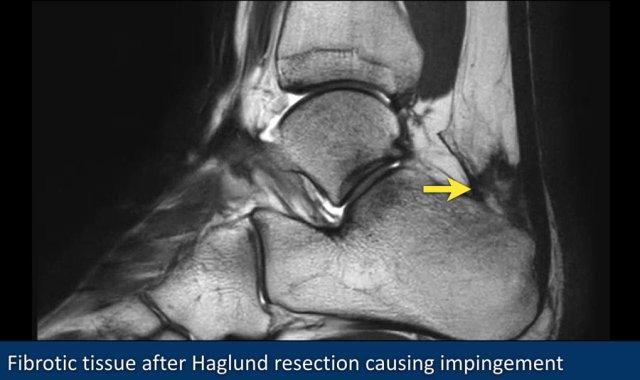

On the right a patient who developed postoperative fibrosis after resection of a Haglund exostosis.

There is fibrosis along the posterior calcaneus and the posterior joint capsule.

This image shows fibrotic tissue anterior to the Achilles tendon (yellow arrow) after resection of a Haglund exostosis.

This was the cause of continuing impingement.